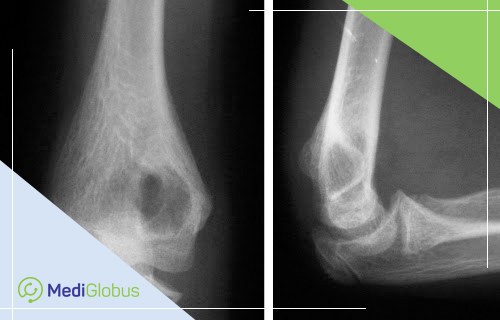

рентген — определяет размер кисты и выявляет риск перелома;

магнитно-резонансную томографию (МРТ) — создает подробные изображения кости, в которой расположена киста;

компьютерную томографию — используется в некоторых случаях для получения более четкого изображения поражения кости;